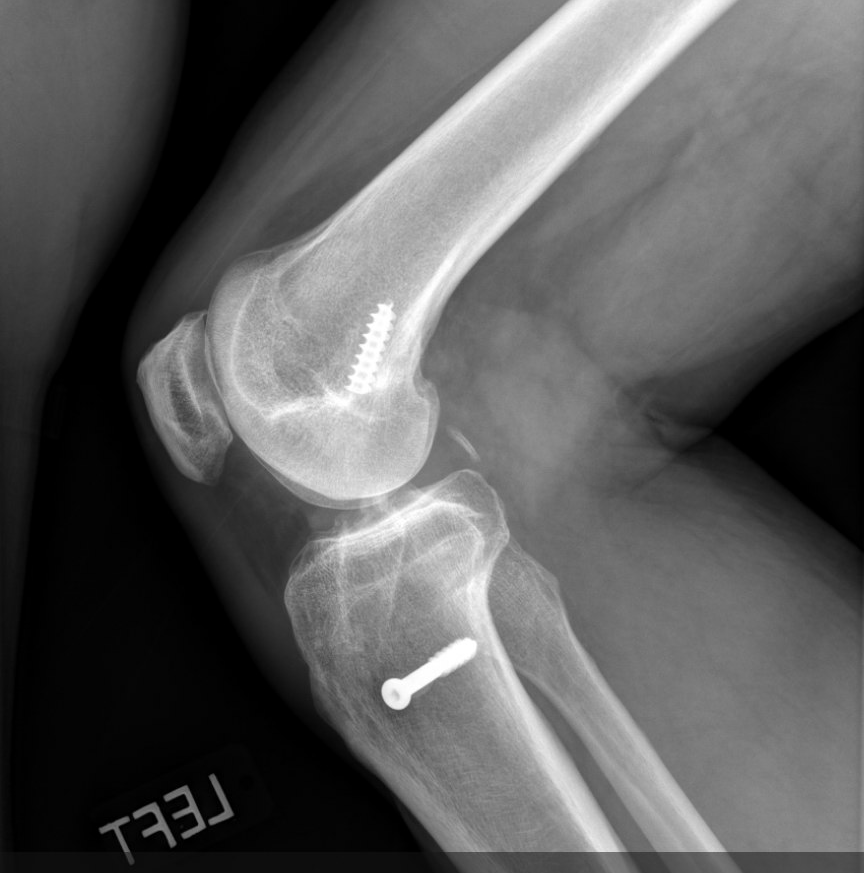

Hello #orthotwitter

55 y/o F, 3 mo post-op, pain with WB since 1 mo.

PMHx unremarkable, non-smoker. Pain constant, ↑ with ambulation, ↓ with rest, ↑ with flexion >90°

Neutrophils 72

ESR 45

CRP 10

PCT normal

Thoughts?

@kneedoclond @EdinburghKnee @aberizzi @drsebheaven